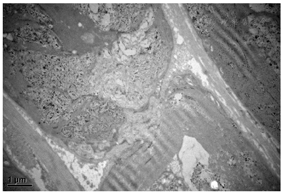

右侧腓肠神经活检病理显示神经束垂直切面,束内大直径有髓纤维轻~中度减少,残存有髓纤维可见轻度髓鞘松解及脱失,个别轴索肿胀变性,未见施万细胞增生或典型洋葱头样结构形成。见图1。电镜下神经束平行切面中郎飞氏结及结旁区可见点片状中等电子致密度物质沉积伴髓鞘终末处结构崩解或脱失。见图2。免疫组化染色:IgG4神经纤维纵切面及横切面中均可见阳性物质呈点灶状沉积于髓鞘,分布不均(图3),CD68(间质及束内极个别+),CD4(血管周及束内少数+),CD8(血管周及束内少数+),CD20(-)。免疫荧光染色示IgG髓鞘灶状阳性(图4),IgA、IgM及补体C1q、C3均为阴性。病理诊断: IgG4阳性的免疫性周围神经病,结合临床及血清学检查,考虑CNTN1抗体相关的CIDP。

在发病机制的研究中显示抗CNTN1-IgG4亚型抗体可穿透至结旁区,封闭CNTN1与其他结旁区蛋白的结合,引发髓鞘终末环松解,其病理表现为朗飞结区延长,结旁区结构破坏,髓鞘终末环从轴索上松解。而没有节段性脱髓鞘、施万细胞增生形成洋葱球样结构等经典型CIDP的病理改变[2,11,12,13,14]。本例患者腓肠神经活检可见大直径有髓纤维轻-中度减少,残存有髓纤维可见髓鞘松解及脱失,轴索肿胀变性,施万细胞轻度变性、增生,未见典型洋葱头样结构形成,结旁区可见点片状中等电子致密度物质沉积伴髓鞘结构崩解或脱失。免疫染色显示髓鞘内点状沉积IgG4免疫阳性物质。以上特点符合CNTN1抗体相关CIDP的病理特点,但很遗憾本病例未进行神经的CNTN1免疫染色,缺少直观的CNTN1抗体沉积的证据。